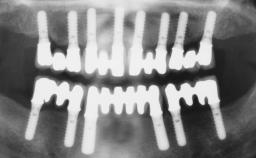

Transition from an “irrational to treat” Maxillary Dentition to a Full-Arch Segmented FDP by Early Loading of Eight Implants Placed Using the Staged Approach

The staged approach permits the transition from an “irrational to treat”dentition to a full arch implant supported restoration without any need to use a removable provisional prosthesis or to apply the immediate-placement and immediate-loading techniques.  A failing dentition is the usual indication for a staged treatment. On the other hand, the dentition should still contain many residual teeth, but with few or none of them being suitable for use as definitive abutments for a full-arch fixed restoration.This situation is usually the result of advanced periodontal disease or of the failure of an extensive fixed prosthesis.

# of Implants 8

Loading Protocol Conventional or early

Interim Prosthesis during Healing Fixed Fixed